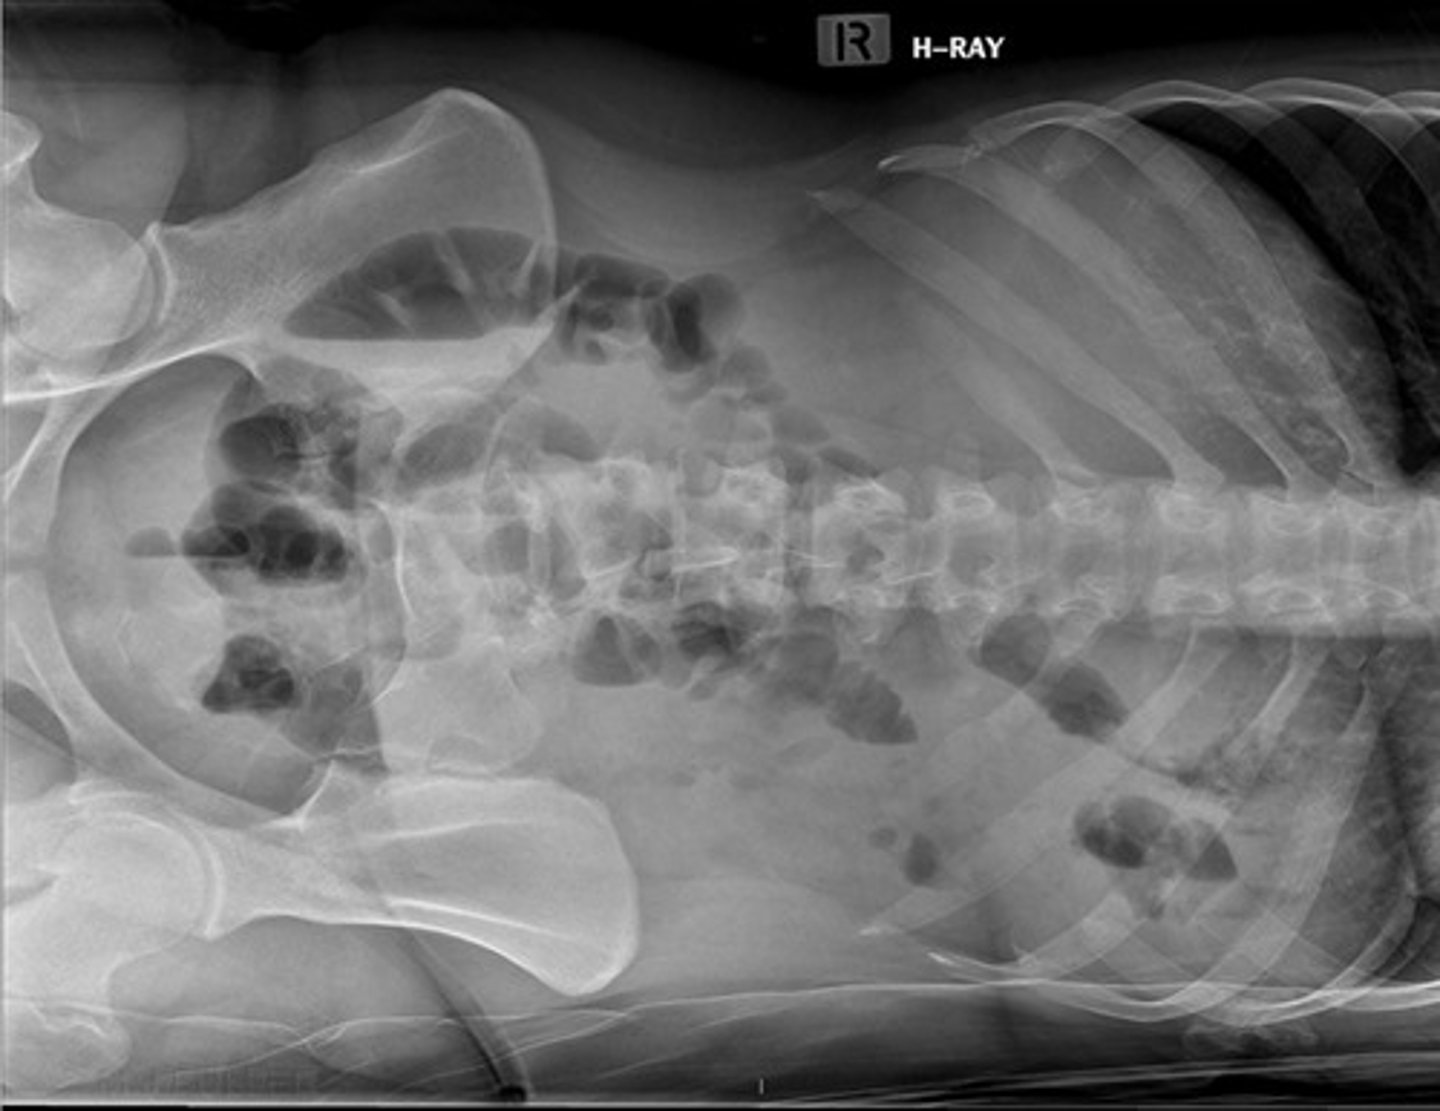

Left lateral decubitus

What view is this image in?